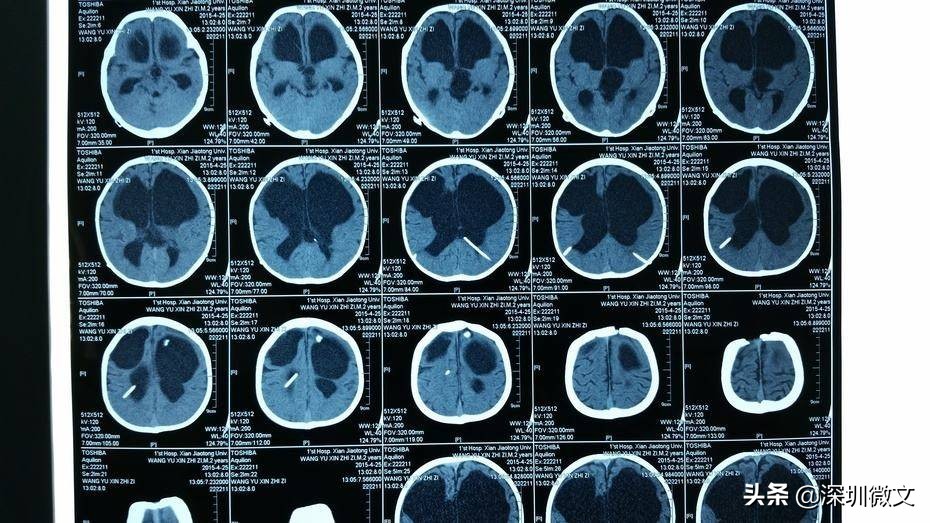

【CT:扫描更具立体感,分辨率更高】

CT正是在这样的医学背景下被研发。CT根本的检查和成像原理与X光相同,但二者最根本的区别在于,X光是将人体的一个或者多个器官投射到同一个平面上进行成像;CT是将人体的一个器官或者多个器官进行一层一层的扫描。

要解释这一点首先还是让我们从“CT”这个名称入手。“CT”的中文全称为“电子计算机断层扫描”。这个所谓的“断层扫描”可以这样理解,在人体的患病部位截取一个长方体,然后再把这个长方体依据不同的层厚与层距分为若干个小长方体进行分别扫描。

这项技术相比X光的突破在哪里呢?X光把前后重叠的肌肉、骨骼、器官全部投射到同一个平面上成像,这就涉及到相互遮挡等问题。这就像你要看一个人的背影,可只有一张正面的照片一样。所以X光的拍摄当中,有患者经常碰到医生要求从不同角度拍摄。

(图)脑部CT片

从X光到CT的突破和进步,我们可以广义的理解为:医生从一个长方形到从一个长方体看病变区域的突破。

除了维度的差别之外,CT另一个重要的进步和突破,在于对病变区域分辨率的差别。举例说明,人体相当的软组织对于X光的吸收量,与水对X光的吸收量很接近。成年人人体体重水占比高达70%,这样一来X光就很难在软组织和人体水分上最终呈现出“黑白色差”——软组织的病变就很容易被忽略。

摄影机要想发现狭小区域内更多的细节,通过什么手段解决呢?增加相机的像素。CT为了发现人体狭小区域的病变,也是增加了CT机器的“像素”。第一代CT机只有1-2个探测器,第二代30个探测器,第三代300-800个,*四代第**1000-2400个。这就像相机的像素越来越高一样,CT机的更新换代,意味着新一代CT机对于荧光细微的差别更加敏感,呈现效果更加清晰——狭小区域的病变细节也就更容易被看到。

由于CT的密度分辨率高,所以软组织、骨与关节都能显得很清楚。除了分辨率更高之外,CT机的又一项重大突破,是可以将各个部位对于X光吸收的差异直接量化。所谓的CT值就是对差异的量化,医生对于病变的判断因此更加准确。

医院里一般都是这个程序,X光没拍出来的,医生会建议再拍CT。最适于CT检查的病是脑部疾病,其中对肿瘤、出血及梗塞等病检查效果最好,其次是腹部实质脏器的占位病变,如肝、脾、胰、肾、前列腺等部位的肿瘤,对乳腺、甲状腺等部位的肿块也能显示并做出诊断;再次则是对胸腔、肺、心腔内的肿块,脊柱、脊髓、盆腔、胆囊、子宫等部位的肿块检查。